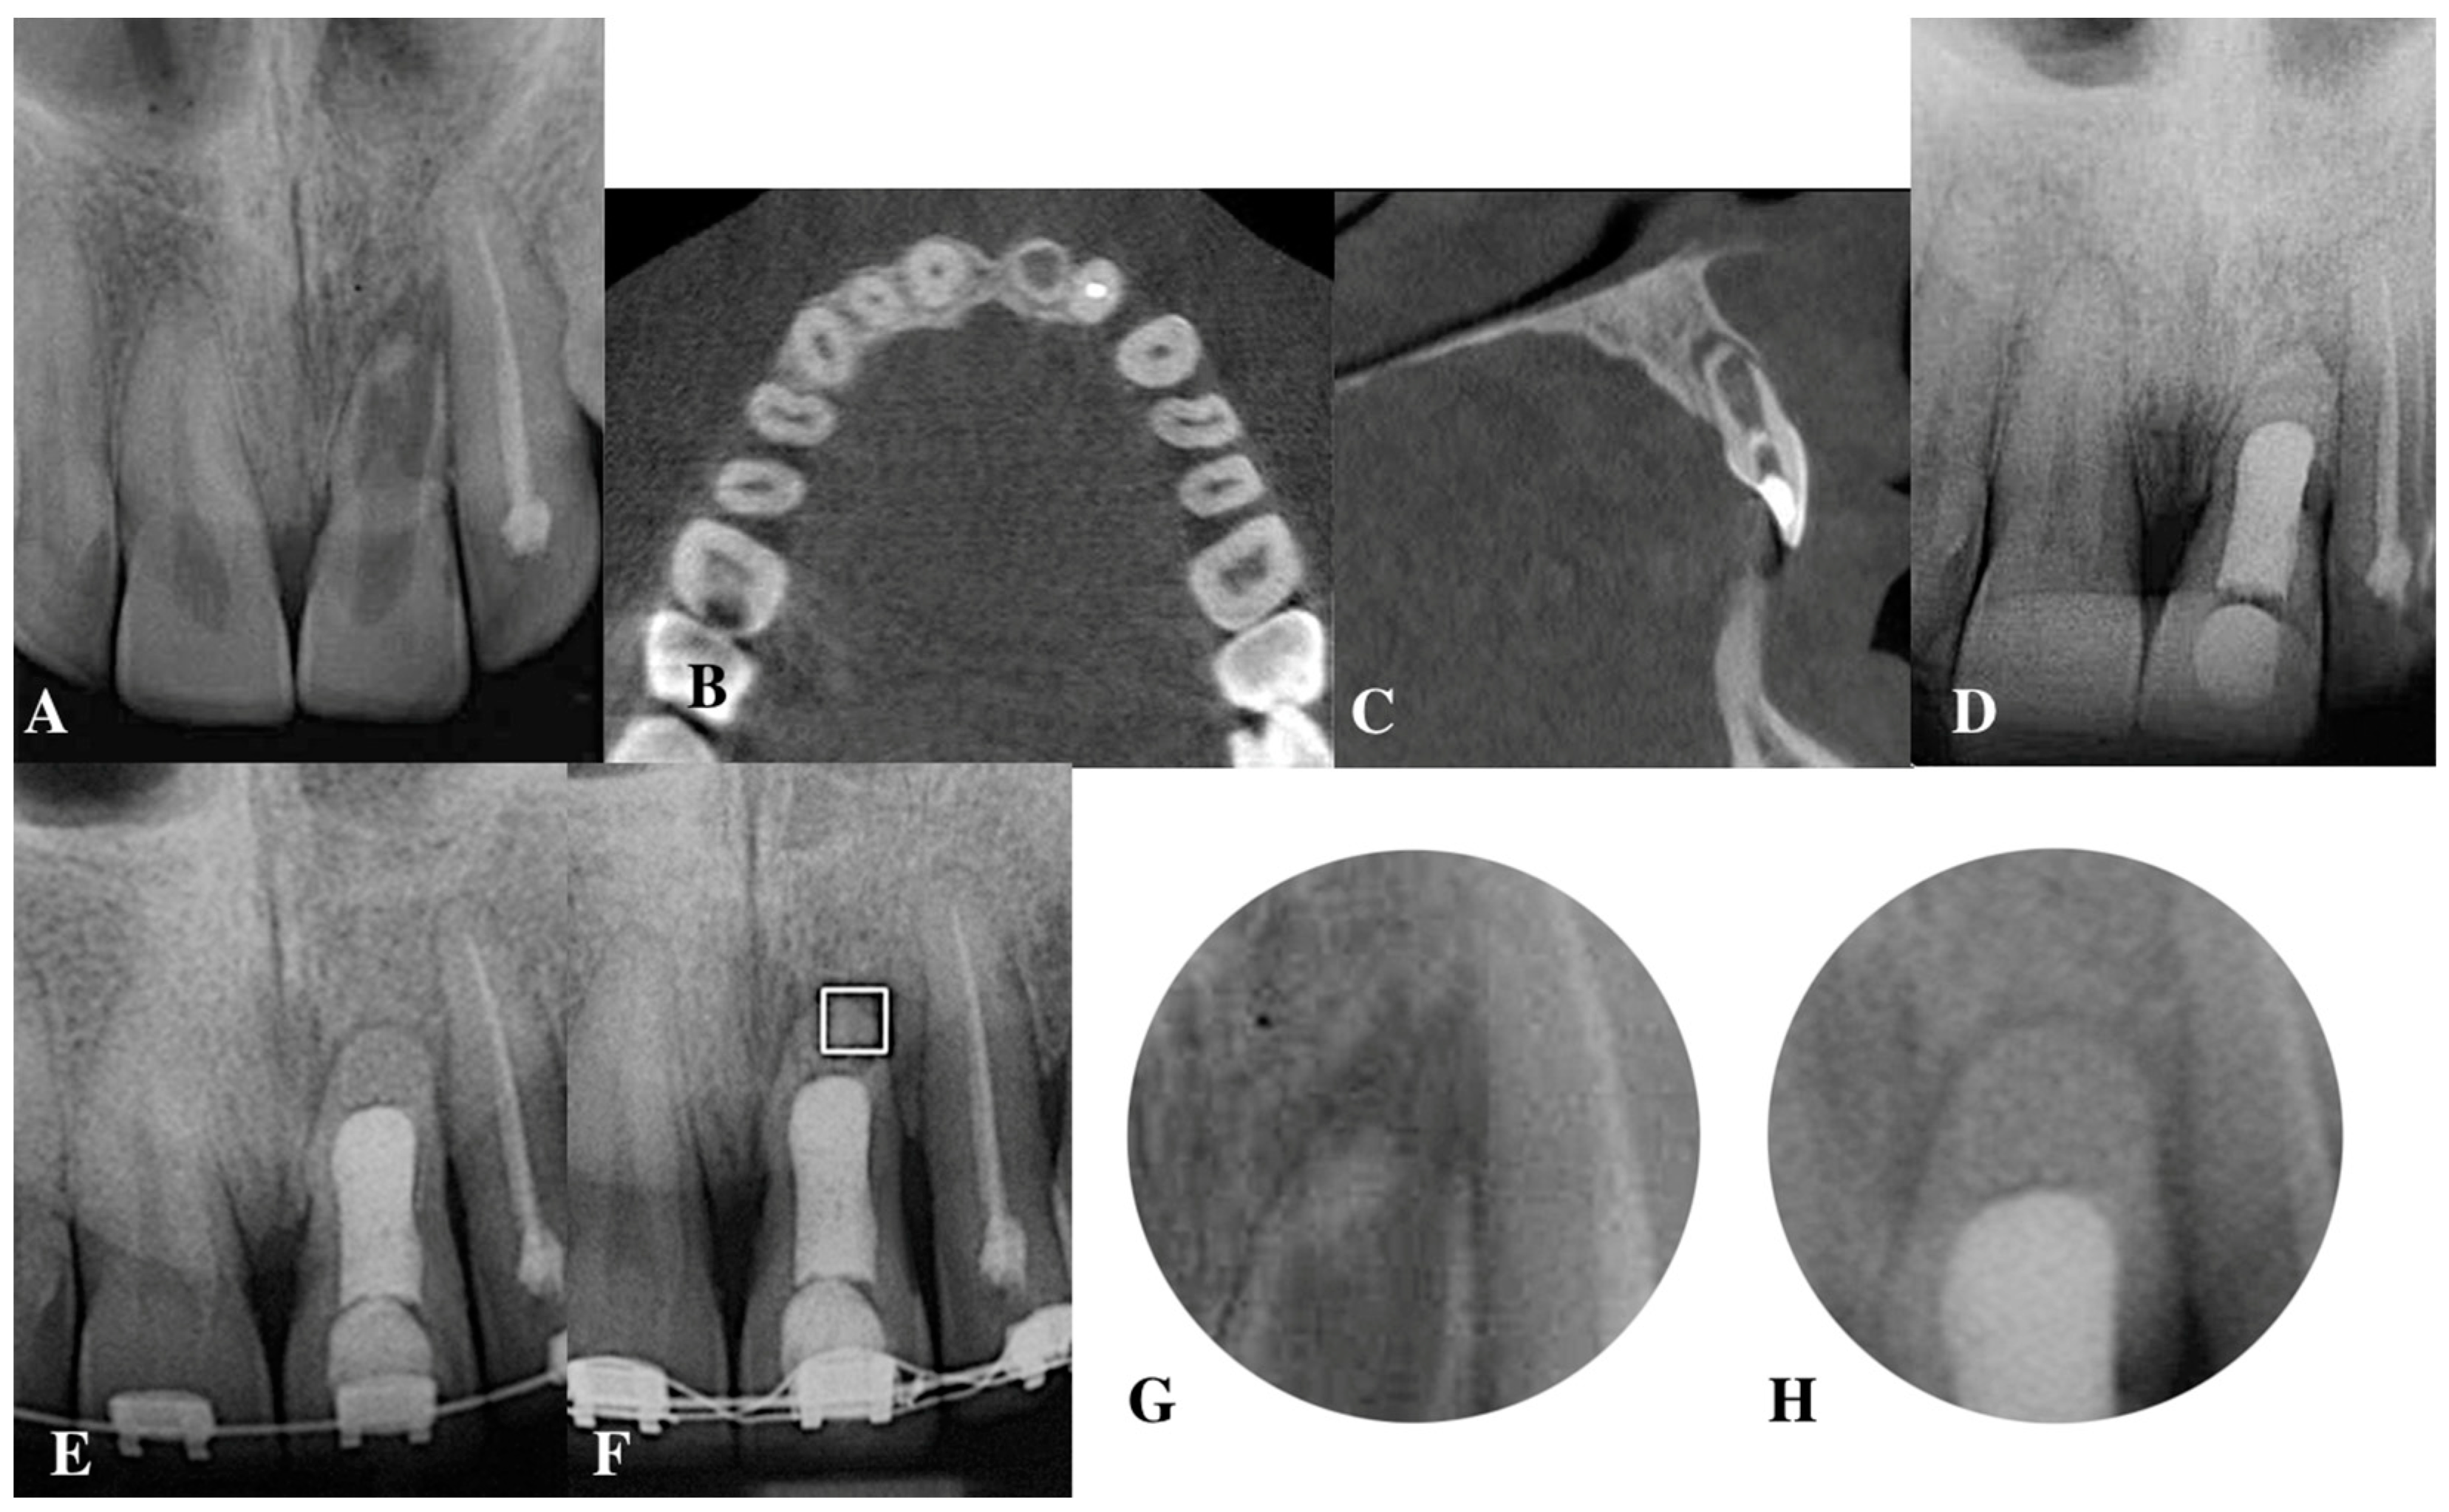

5.1. Apical Plug in Teeth with Apical Resorption and “Open Apex”

5.2. Apical Barrier